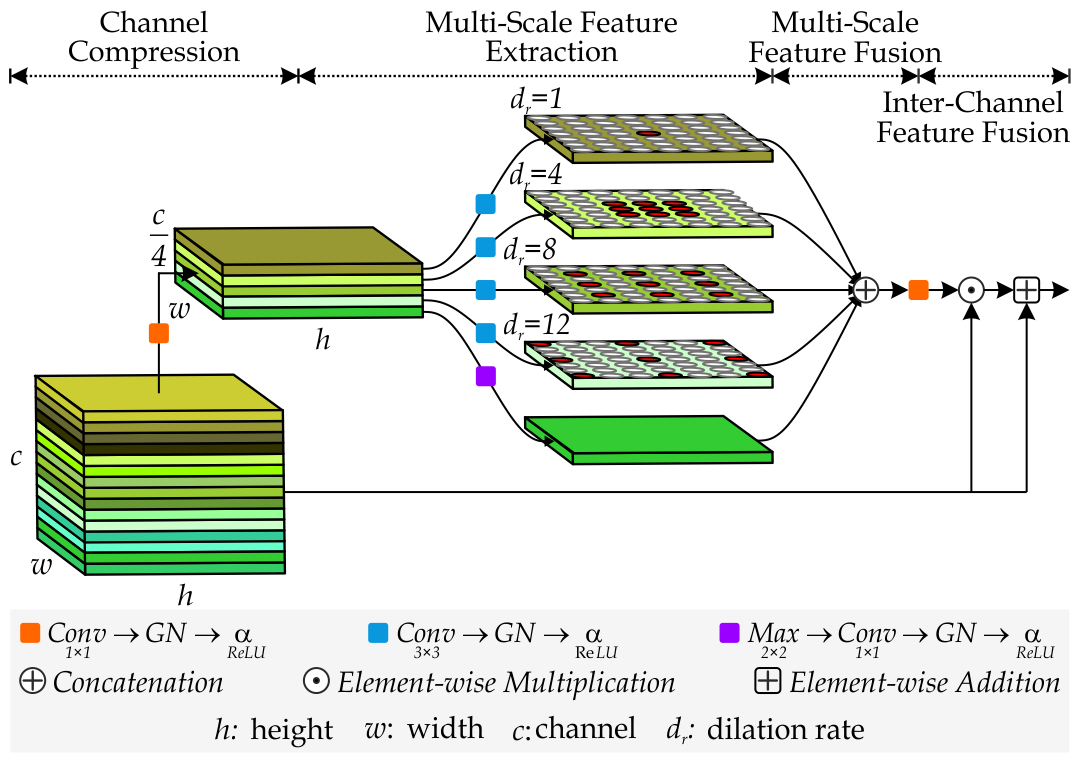

3.4.1 Multi-Scale Feature Aggregator Unit

Colonoscopy image analysis often assumes that specific features reside at specific scales [33]. However, existing multi-scale approaches primarily focus on feature extraction [33], neglecting aggerated channel-spatial dimensions. To mitigate this, we introduce a Multi-Scale Feature Aggregator (MSFA) Unit that integrates Squeeze-and-Excitation (SE) blocks [29] after multi-scale feature extraction and aggregates them. This emphasis on salient regions enhances the polyp’s feature representation.

The MSFA unit receives the output of the encoder’s final EGFE unit, , as input. It then processes this feature map through multiple convolutions with varying dilation rates, as defined mathematically in Eq. 3.

| (3) |

Here, we define as the location on the feature map, as the dilation rate, as the th parameter of convolution filter, and signifies the filter size. Eq. 3 illustrates varying dilation rates enables the acquisition of diverse receptive fields, serving as multiple scales to learn spatial components. Afterward, we recalibrate these multi-scale features through the SE block to prioritize the relevant multi-scale features. By concatenating these multi-scale aggregated features with distinct receptive fields, MSFA generates high-level contextual features. The following equations represent the mathematical formulation of MSFA.

| (4a) |

| (4b) |

Here, represents the multi-scale features captured at different dilation rates enhanced by SE block, denotes the concatenated multi-scale features which are further processed by , ReLU activation function. Finally, all concatenated features are processed through convolution with kernel to generate final multi-scale aggregated features, denoted by .

3.4.3 Channel-Enhanced Atrous Spatial Pyramid Pooling

To improve polyp representation by resampling features at different scales, we propose Channel-Enhanced Atrous Spatial Pyramid Pooling (CE-ASPP). Unlike the standard Atrous Spatial Pyramid Pooling (ASPP) [34], which uses dilated convolutions for multiscale extraction and standard convolutions for fusion, CE-ASPP incorporates a three-step refinement to recalibrate the importance of various feature channels adaptively.

Within CE-ASPP (refer to Fig. 5), we first compress the input feature channels by a factor of four. This compression is then reversed before the final output is generated (refer Eq. 7).

| (7) |

Here, denotes the ReLU activation function, is the channel-compressed features, and GN is Group Normalization [35], chosen for its accuracy stability across batch sizes.

Secondly, undergoes five parallel routing convolutions: four with depth-wise atrous convolutions (dilation rates 1, 4, 8, and 12) and one with max-pooling followed by point-wise convolution for salient feature extraction and channel dimension adjustment. This process is expressed below:

| (8a) | |||

| (8b) | |||

where, and denote the compressed multi-scale features obtained from atrous convolutions (varying dilation rates) and max-pooling, respectively. Lastly, Multi-scale and inter-channel fusion are then applied to generate as expressed in Eq. 9 and Eq. 10.

| (9) |

| (10) |

Here, denotes the concatenated multi-scale features. and represent element-wise multiplication and addition, respectively. The CE-ASPP module generates the final feature, is fed into the decoder.

Effect of MSFA Module:

To gain insights into the MSFA module, we initially extract features at multiple scales , resulting in a DSC of 93.52%, integrating the SE block after multi-scale feature extraction further improves DSC, IoU, Pre, and Rec. The SE block prioritizes informative features from extracted multi-scale extraction. Replacing the convolution kernel with a kernel in MSFA further improves performance, yielding a 3.09% and 3.20% increase in DSC and IoU, respectively, as highlighted in Table 4. The results highlight the importance of the MSFA module in capturing crucial features for polyp segmentation.

| Methods | DSC|∇| | IoU|∇| | Pre|∇| | Rec|∇| |

| MNet-SAt | 93.52 | 93.72 | 93.58 | 94.03 |

| MNet-SAt | 95.16 | 95.58 | 96.14 | 95.92 |

| MNet-SAt | 96.07 | 95.93 | 96.74 | 96.73 |

| MNet-SAt | 96.61 | 96.92 | 97.36 | 97.12 |

| : dilation rate, SE: Squeeze & Excitation, : kernel Conv Operation | ||||

Effect of CE-ASPP:

An ablation study in Table 6 evaluates the contributions of Multi-Scale Feature Fusion (MSF), Channel Compression (CC), and Inter-Channel Feature Fusion (ICF) within the CE-ASPP module. We observe that incorporating CC and MSF outperforms utilizing MSF alone but remains less effective than the MNet-SAt framework. Specifically, combining MSF with ICF (i.e., w/o CC) yields better results than combining CC with MSF. This enhanced performance is attributed to ICF, strengthening the framework’s ability to capture complex dependencies between feature channels.

| Methods | DSC|∇| | IoU|∇| | Pre|∇| | Rec|∇| |

| MNet-SAt | 94.21 | 94.76 | 94.39 | 95.05 |

| MNet-SAt | 95.32 | 95.41 | 96.52 | 95.87 |

| MNet-SAt | 95.89 | 96.27 | 97.08 | 96.54 |

| MNet-SAt | 96.61 | 96.92 | 97.36 | 97.12 |

| MSF: Multi-Scale Feature Fusion, CC: Channel Compression, ICF: Inter-Channel Feature Fusion | ||||